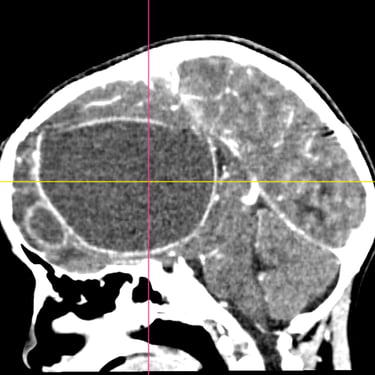

El absceso cerebral es una infección localizada del parénquima cerebral que produce acumulación de pus e inflamación, generando cefalea, fiebre, alteración del estado de conciencia o déficit neurológico focal. El diagnóstico temprano es fundamental para evitar complicaciones graves. La tomografía cerebral con contraste es el estudio de elección inicial, ya que permite visualizar una lesión hipodensa con realce en anillo característico. Posteriormente, la resonancia magnética complementa la evaluación. El tratamiento combina antibioticoterapia dirigida y, en casos seleccionados, drenaje quirúrgico o resección. La detección oportuna mediante imágenes mejora significativamente el pronóstico del paciente.